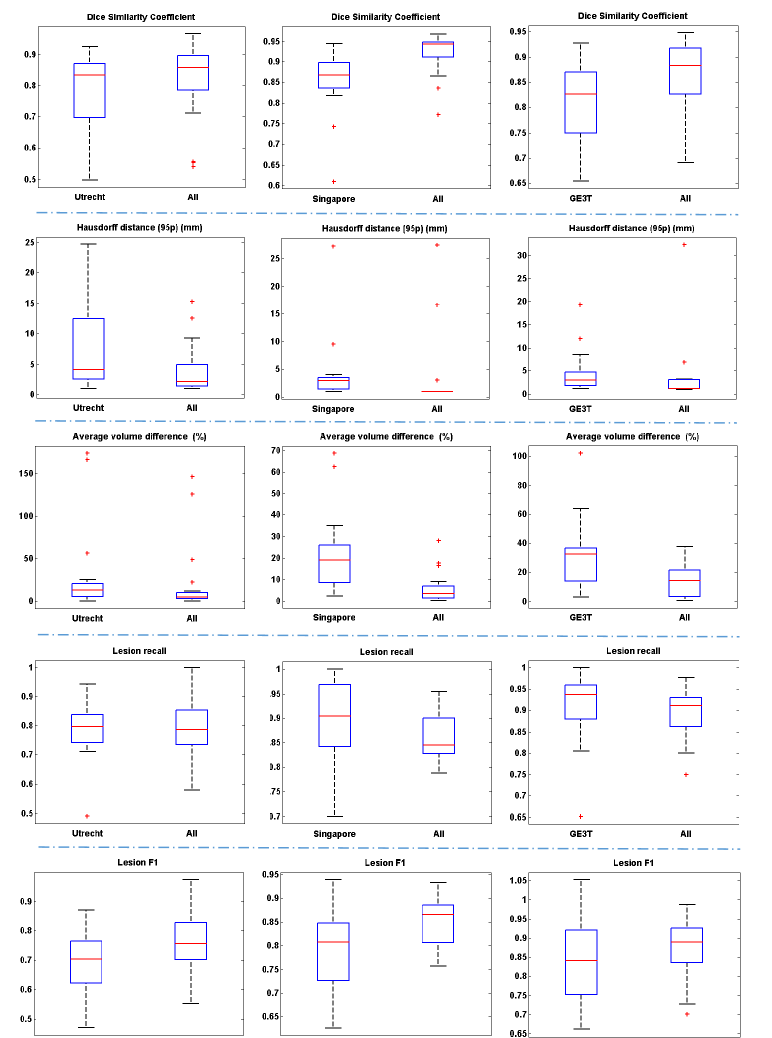

Figure 6 plotted the distributions of segmentation performances on scans from the three scanners, with each sub-figure showing performances using one of the five metrics. It could be observed that the segmentation performance on Utrecht was relatively poor. A few outliers (hard examples) were found in Utrecht which appeared to contain relatively more small lesions and blurred slices after checking the original slices and segmentation results. Section 5 presents a further analysis of these outliers, revealing the challenge of WMH segmentation task. In general, the averaged dice similarity coefficient, Hausdorff distance and lesion recall achieved by the proposed system on 60 cases were 87%, 3.6mm and 85%, respectively. This shows its effectiveness in aspects of overlapping, localization accuracy and overall lesion detection. Table S1 in the supplemental material reports extensive results allowing comparison on every case of the public training dataset.

Figure 7 plots the distributions of segmentation performances on cases from each scanner being tested in turn, with each sub-figure showing performances using one of the five metrics. In general, for every 20 cases from each of the three testing scanners in the cross-scanner evaluation, the segmentation result between each other was comparable, showing our system is robust to unseen scanners. It could be observed that the segmentation performance on dataset GE3T was relatively poor. This could be explained that the voxel size of cases in GE3T has a significant difference from that captured by two other scanners. Combination of modalities will be discussed in Section 5.3 Table 6 compares the segmentation performances of the top performing teams on two unseen scanners. Our method achieved, on average, the best Dice similarity coefficient and lesion recall of 74.5% and 87% respectively and runner-ups on other three metrics.

Figure 12 shows box plots of performances on each dataset. Interestingly, we observed that, on four metrics - dice similarity coefficient, Hausdorff distance (95p), average volume difference and lesion F1-score, the model trained on three scanners achieved significant improvement over the one trained on single scanner. However, on lesion recall, the model trained on single scanner gained slightly better segmentation performance. This was due to the decrease of the number of undetected small lesions. We concluded that the network trained on the larger data set that included cases obtained from different scanners shows better prediction performance, but at the cost of a sensitivity towards small lesions that were still detected best by networks trained on scanner- or sequence-specific data.